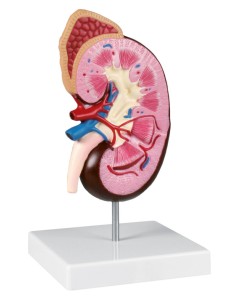

Dal cranio in 22 parti con incastri magnetici ai modelli di colonna vertebrale, da quelli di articolazioni a quelli di cuore, ogni pezzo della nostra collezione è progettato per un’immersione totale nello studio dell’anatomia umana. I nostri modelli, realizzati tramite scansioni di ossa vere, garantiscono un’esperienza tattile autentica e una fedeltà di peso quasi identica agli originali.

Essenziali per studenti e professionisti, i nostri modelli anatomici sono strumenti didattici che permettono di osservare le strutture anatomiche con precisione, eliminando la necessità di dissezioni o studi invasivi. Sono inoltre utili per spiegare ai pazienti le patologie, rendendo la comunicazione più efficace e risparmiando tempo prezioso.